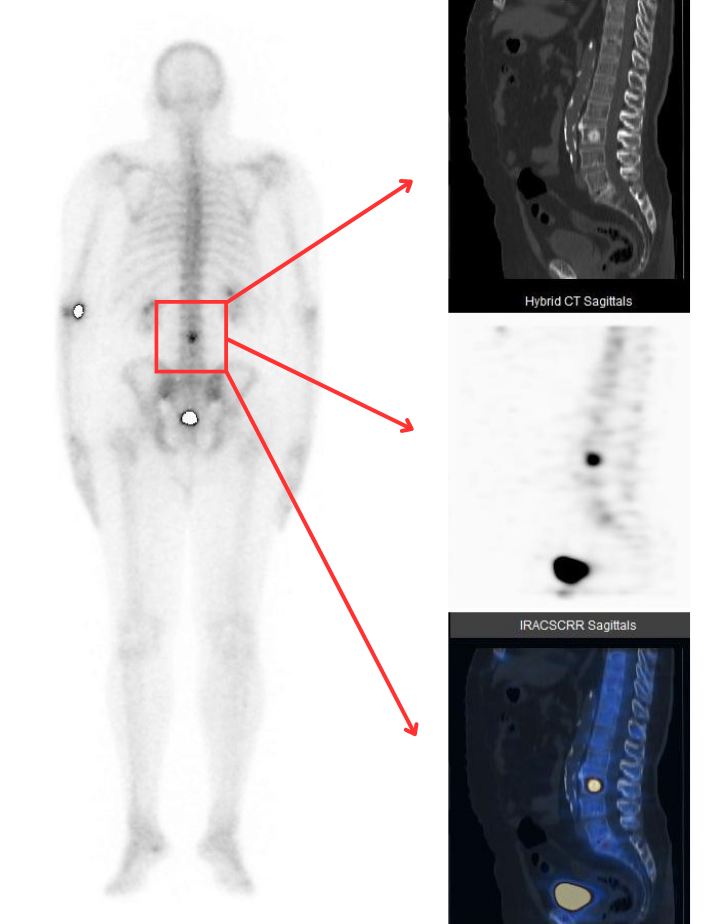

Il Servizio di Medicina Nucleare di Humanitas Istituto Clinico Catanese ha compiuto un grande salto in avanti nell’imaging diagnostico grazie all’acquisizione di una nuova gamma camera di ultima generazione, un tomografo ibrido che unisce le funzionalità di una gamma camera e di una TC: la SPECT/TC. La gamma camera è dotata di caratteristiche peculiari (detettori Slim Elite NXT compatti, wide gantry, robotica ultra-fast) che permettono di ottenere le massime performance nell’esecuzione delle indagini scintigrafiche sia in termine di “qualità” delle immagini diagnostiche che in termine di “riduzione” della dose di radiofarmaci necessari.

“La robotica ultra-fast del tomografo – dichiara il dott. Demetrio Aricò, responsabile del Servizio – consente di configurare il tomografo ibrido non solo in base alla tipologia dell’esame, ma anche in base alle necessità cliniche del paziente: acquisizioni in piedi, su barella o seduti. È la macchina che si adatta al paziente e non il contrario. L’altro grande vantaggio ottenuto con il nuovo tomografo è la SPECT/TC, nuova tecnica di acquisizione delle immagini che garantisce un significativo incremento dell’accuratezza diagnostica delle indagini scintigrafiche.“

Esattamente come avviene per l’imaging PET, il paziente potrà eseguire al termine della scintigrafia – che dura circa 3-15 minuti – una scansione TC senza scendere dal tomografo permettendo al Medico Nucleare di giungere alla conclusione diagnostica in modo veloce ed accurato. Il percorso diagnostico, in questo modo, diventa estremamente più breve in quanto non ci sarà più bisogno di eseguire un ulteriore approfondimento radiologico dopo la scintigrafia, già compreso nella scintigrafia stessa! Il paziente, grazie all’utilizzo del nuovo tomografo, non non dovrà più eseguire due esami distinti e separati in giorni differenti.

“Le immagini sono paragonabili a quelle delle PET – prosegue Aricò – ma con alcune differenze in quanto la SPECT/TC è eseguita solo in caso di necessità (come approfondimento richiesto dal Medico Nucleare) e solo sul distretto interessato come il torace, l’addome, il cervello, ecc., ottimizzando le tempistiche e il comfort del paziente. La SPECT/TC è molto utile in diverse applicazioni cliniche e coinvolge trasversalmente molte discipline mediche come la cardiologia, l’ortopedia, l’endocrinochirurgia, le malattie infettive ed anche la neurologia.“